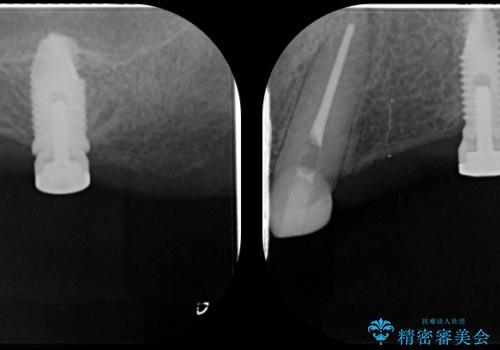

インプラント支台のマグネットを用いることで安定してしっかりと噛めるような総義歯治療を計画します。

- 100万円(インプラント・マグネットアバットメント×3・金属床義歯)費用は治療当時の料金となります

通常の入れ歯は歯ぐきで支えるため話したり食事の際に動いたり安定が悪くなってしまうことが多いですが、インプラント支台のマグネットを設定することでより安定してしっかりと噛むことができるようになります。